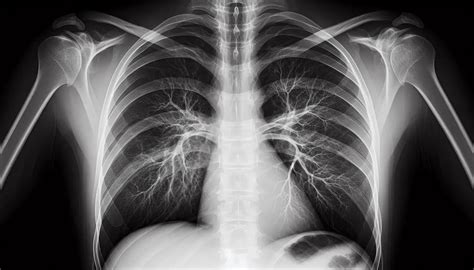

Tipos de Radiografías Utilizadas en el Diagnóstico Periodontal

- Radiografía periapical: Esta radiografía muestra las raíces de los dientes y el hueso que las rodea. Es crucial para observar la pérdida ósea y detectar problemas en las raíces dentales causados por la enfermedad periodontal.

- Radiografía panorámica: A diferencia de la periapical, la panorámica captura una visión general de toda la boca, lo que permite al dentista obtener una visión más amplia del estado de las encías y el hueso de la boca.